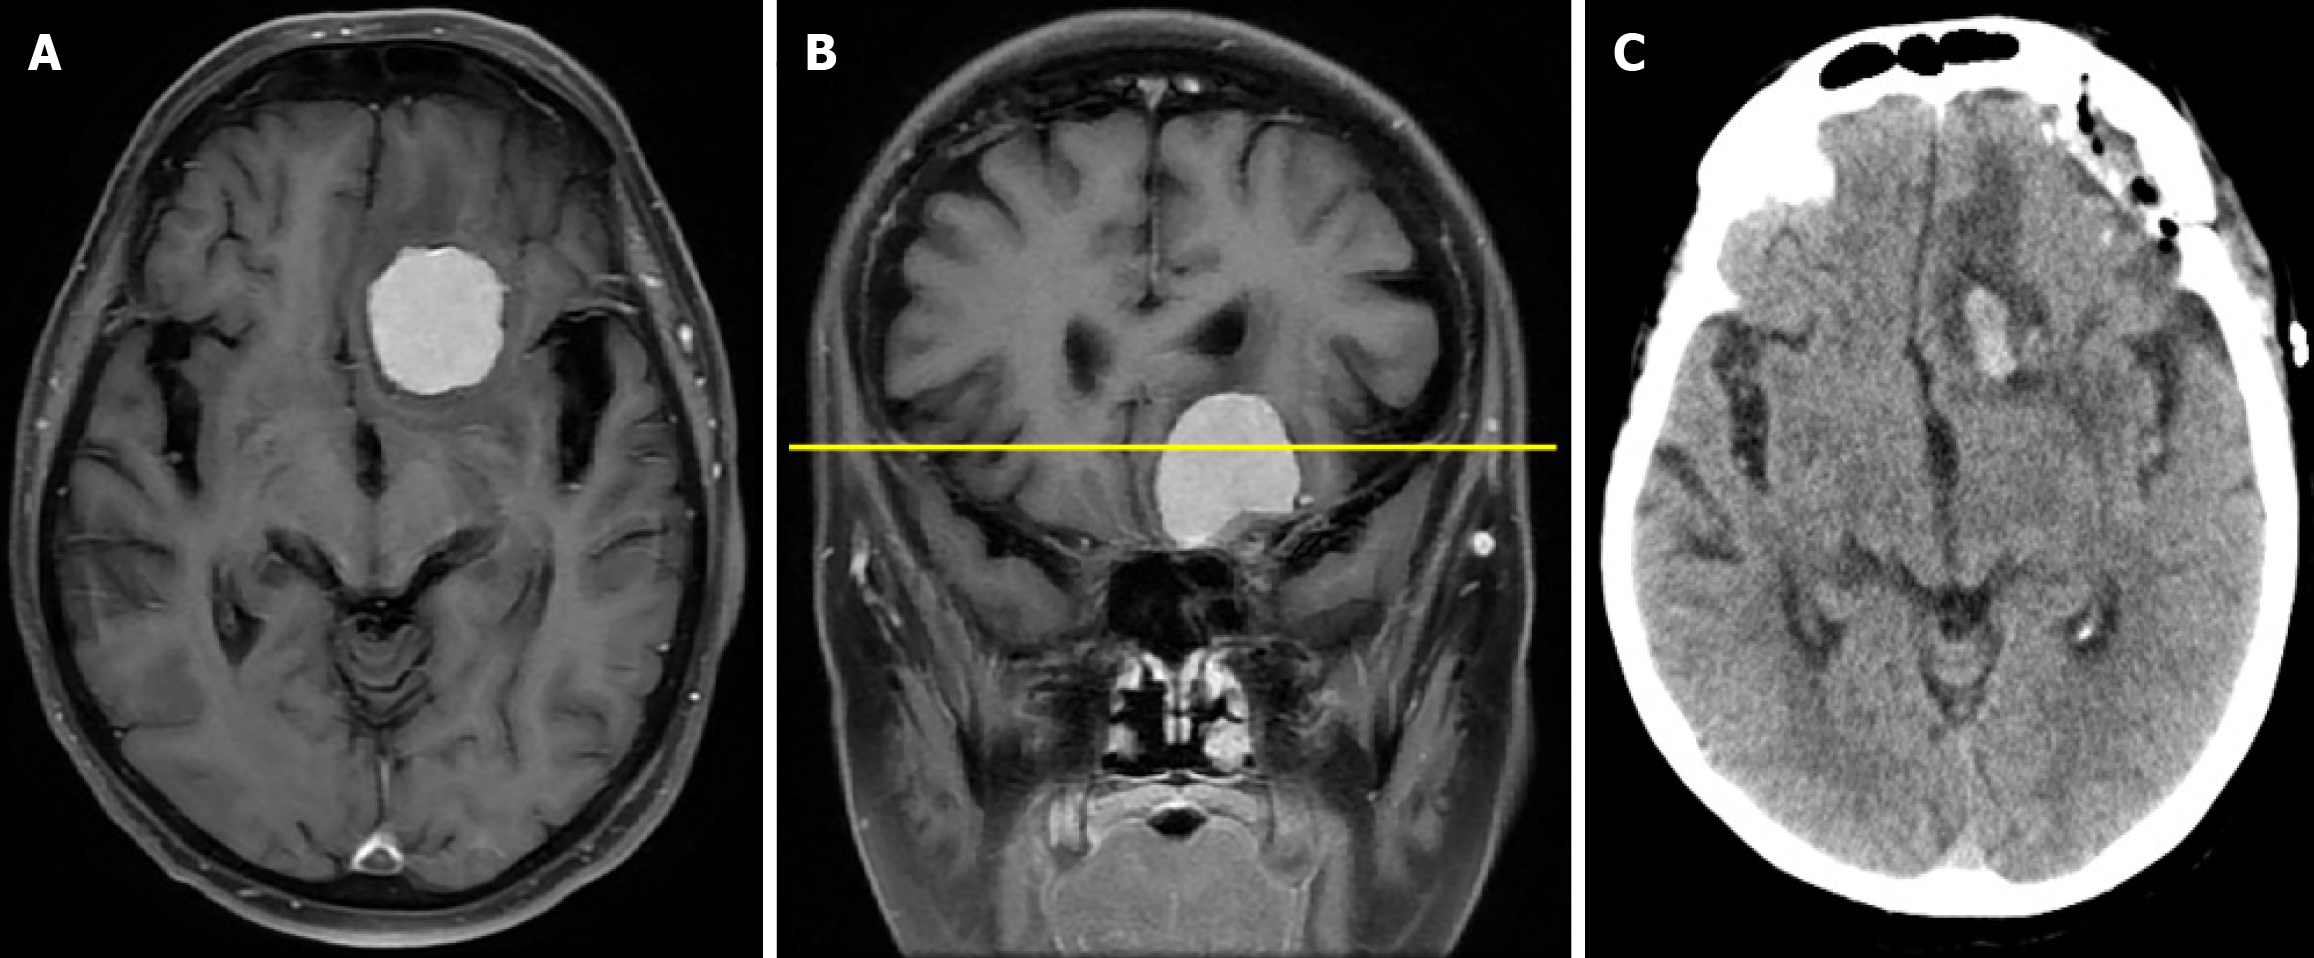

Figure 1 Cranial computed tomography and magnetic resonance imaging.

A: Contrast-enhanced axial T1-weighted magnetic resonance image demonstrating an anterior cranial fossa meningioma with mass effect on the left frontal lobe; B: Coronal magnetic resonance image confirming the frontobasal location of the lesion; C: Postoperative cranial computed tomography scan showing satisfactory postoperative findings.